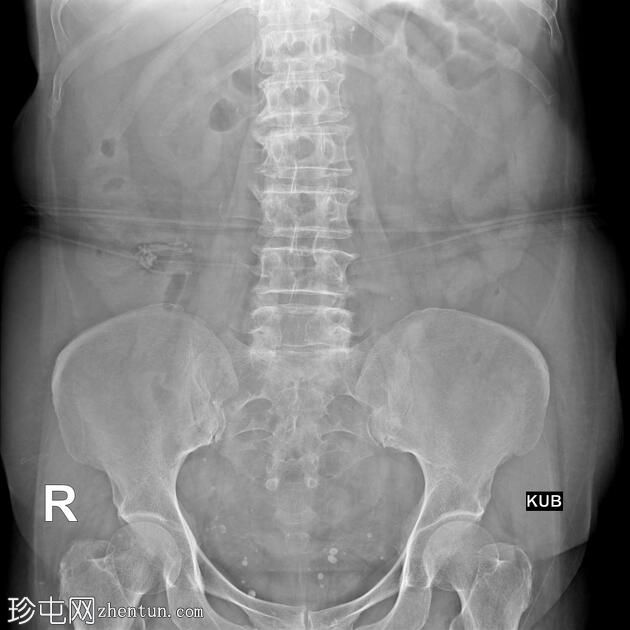

结肠异常表现包括结肠袋皱襞消失,使其外观模糊,呈铅管样改变。

其他异常表现包括降结肠和乙状结肠肠袢狭窄,以及横结肠和降结肠多处黏膜糜烂(双对比增强图像可见)。

未见肿块或瘘管形成。

升结肠外观正常,结肠袋皱襞完整。